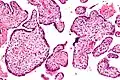

Histomorphologically, VUE is characterized by a lymphocytic infiltrate of the chorionic villi without a demonstrable cause. Plasma cells should be absent; the presence of plasma cells suggests an infective etiology, e.g. CMV infection.

Intermed. mag.

High mag.